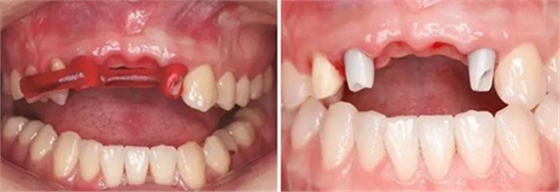

圖17 CBCT測(cè)量骨量變化 圖18 早期修復(fù)戴牙當(dāng)天

圖19 早期修復(fù)1月 圖20 早期修復(fù)2月

圖21 早期修復(fù)3月 圖22 早期修復(fù)3月打開三角間隙

圖23 早期修復(fù)4月 圖24 早期修復(fù)7月切除軟組織增生后

圖25 早期修復(fù)7月調(diào)改橋體部形態(tài)為卵圓形并高度拋光 圖26 早期修復(fù)8月

圖27 早期修復(fù)8月調(diào)改后 圖28 早期修復(fù)10月

(4)2015年3月—2015年12月:早期修復(fù)伴軟組織誘導(dǎo)成形對(duì)患者制取開窗印模后,使用橋用金屬臨時(shí)基臺(tái),制作聚甲基丙烯酸甲酯(PMMA,登士柏公司,德國(guó))經(jīng)CAD/CAM切削的臨時(shí)修復(fù)橋體,戴入臨時(shí)修復(fù)體對(duì)牙齦軟組織進(jìn)行誘導(dǎo)成形,采用動(dòng)態(tài)加壓技術(shù),最初緩慢戴入臨時(shí)修復(fù)體,撐開牙齦軟組織袖口,擠壓粘膜,粘膜受到擠壓后缺血變白,10min內(nèi)可恢復(fù)為粉紅色。臨時(shí)修復(fù)體為縱向螺絲固位,便于拆卸調(diào)改形態(tài),囑患者勿用臨時(shí)修復(fù)體咬物,注意口腔衛(wèi)生,用牙線或沖牙器等將種植體周圍清潔干凈,每月進(jìn)行復(fù)查,不斷調(diào)改臨時(shí)冠的穿齦形態(tài),讓出軟組織生長(zhǎng)空間,直至誘導(dǎo)牙齦形成類似于天然牙的穿齦袖口形態(tài)。其中在早期修復(fù)3月時(shí),通過打開修復(fù)體間的三角間隙,以讓出齦乳頭生長(zhǎng)的空間;在早期修復(fù)7月時(shí)對(duì)22位點(diǎn)唇側(cè)牙齦根方的軟組織增生物進(jìn)行刮除并縫合,同時(shí)將修復(fù)體的橋體部位調(diào)磨成卵圓形的蓋嵴部并高度拋光,以獲得良好的橋體部軟組織形態(tài),形成健康、連續(xù)且協(xié)調(diào)的軟組織輪廓。